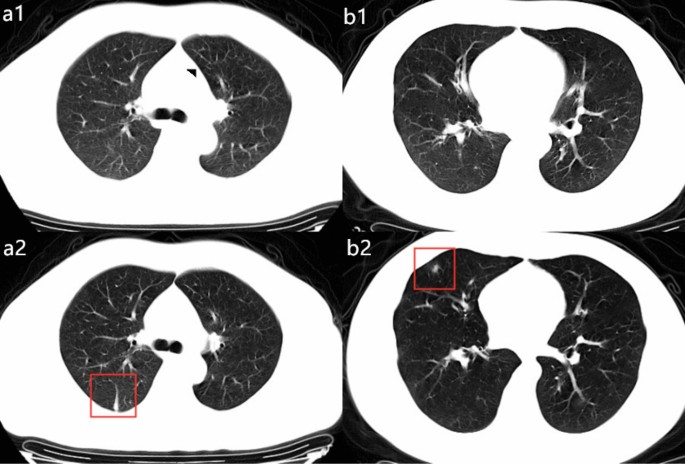

Among the 172 discharged patients with confirmed COVID-19, the average time from symptom onset to discharge was 20.48 ± 8.22 (ranging from 3 to 50), with a median number of 19 days. The time from onset to the discharge of all patients is illustrated in Fig. 2. We divided the 172 patients into two groups based on the time from onset to discharge. A total of 96 patients (55.8%) who had time from onset-discharge no more than 19 days were assigned to group 1. A total of 76 patients (44.2%) who had longer time onset-discharge (more than 19 days) were assigned to group 2. The demographic and clinical characteristics of the patients according to the groups are summarized in Table 1. In the full cohort, there were 97 males (56.4%) and 75 females (43.6%), with a mean age of 43.9 years (SD: 14.8). There was no statistically significant difference in the age (p = 0.060), gender (p = 0.790) or current smoking history (p = 0.241) between the groups. History of direct exposure to Wuhan was documented in 48.8% of patients; the remaining 51.2% of patients had contact with people from Wuhan and there was no significant difference between the two groups (p = 0.376). There were 11 patients (11.5%) in group 1 and 6 patients (7.9%) in group 2 who had an admitting diagnosis of non-pneumonia (p = 0.437). Several non-pneumonia patients had longer hospitalization days owing to persistent symptoms or pneumonia occurrence during admission. Their CT images were initially normal but abnormalities occurred during admission (Fig. 3).

Examples of patients with admitting diagnosis as non-pneumonia in Group 2. (a1–a2) a 45-year-old man with confirmed with non-pneumonia COVID-19 and had hospitalization days of 16. Patients had fever at onset of disease, but normal CT images at the beginning of the admission (a1), at 4th day on admission, the follow-up CT images demonstrated inflammatory appearance as linear shadowing (a2). (b1–b2) a 31-year-old man diagnosed as non-pneumonia with COVID-19 who had cough at onset but normal CT images (b1). Total hospitalization time was 18 days. After 4 days admission, an irregular consolidate nodule can be seen in the right middle lobe from the follow-up CT images (b2).